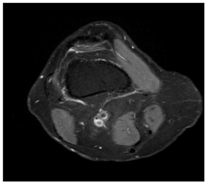

In this section, we present and analyze the results obtained with the proposed method, and compare it to methods proposed in similar works. The proposed watermarking system is implemented using MATLAB and executed on a Windows machine with the following characteristics: Intel R Core i5 processor, 4 GHz, 4 GB RAM, and Microsoft Windows 8 Professional operating system platform. In our experiments, we have used DICOM images of size 512 × 512 pixels as shown in Table 1.

Table 1.

Original images.